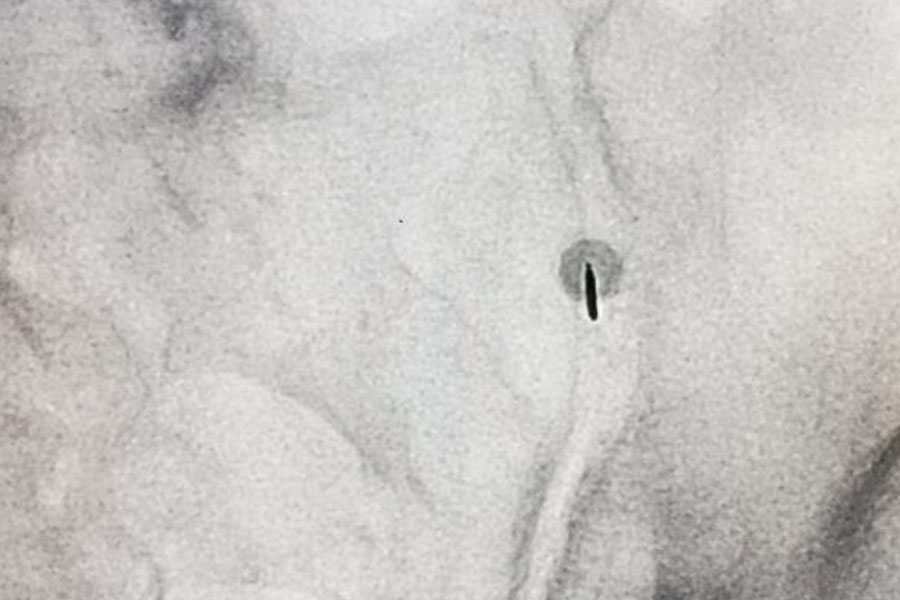

Treatment is primarily conservative, based on physiotherapy and pain relieving/anti-inflammatory drugs. In resistant cases, intra-articular infiltrations, under ultrasound or fluoroscopic guidance, of slow-release cortisone, are an effective approach. In case of mechanical instability, the benefit may be temporary, in these cases it is possible to resort to sensory denervation of the sacroiliac joint with radiofrequency (RF) which can provide a long-lasting pain relief.